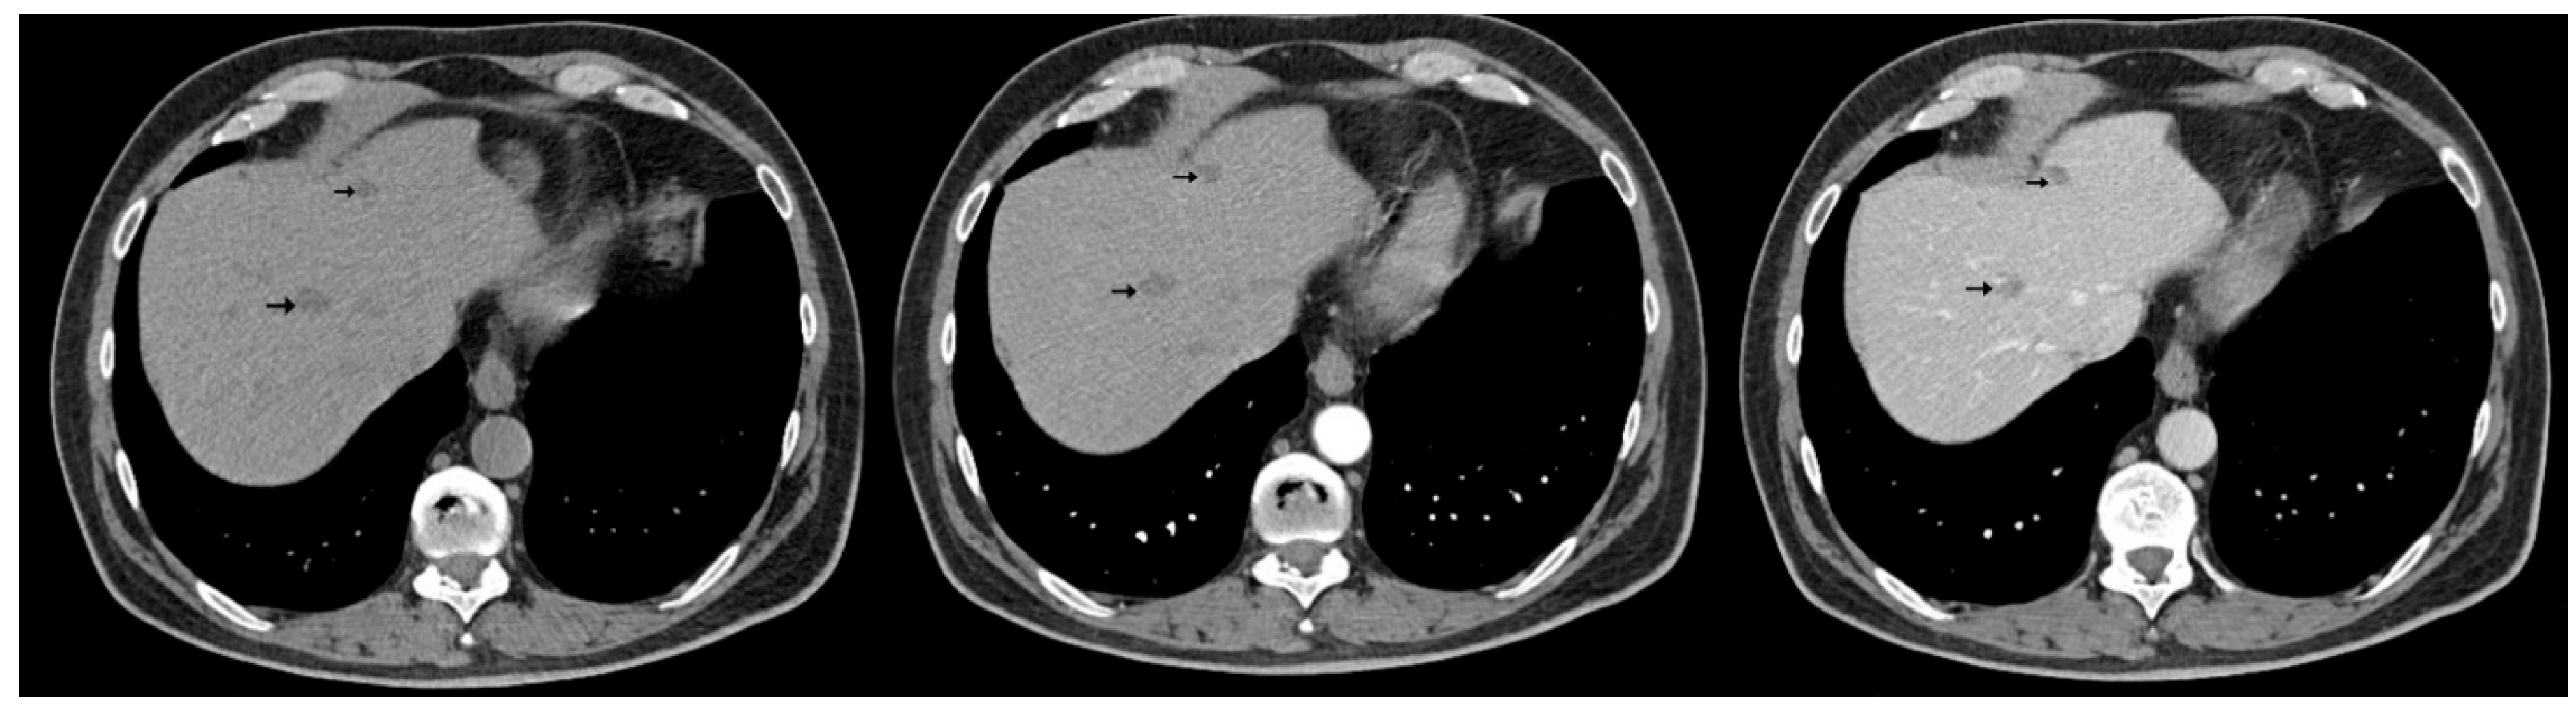

The abdominal contrast-enhanced CT scan further revealed multiple hepatic hypodense nodular lesions, measuring between 1 cm and 3 cm (Figure 6 and Figure 7).

Figure 6.

Contrast-enhanced abdominal CT (axial, non-contrast phase—left, arterial phase—center, and portal venous phase—right) shows liver sections with hypodense nodule in IVa hepatic segment exhibiting arterial-phase enhancement similar to background parenchyma and washout on the portal venous phase, measuring 1–3 cm (arrows).

Figure 7.

Contrast-enhanced abdominal CT (axial, non-contrast phase—left, arterial phase—center, and portal venous phase—right) demonstrates two hypodense hepatic nodules (black arrows) with a pseudocapsule appearance—more conspicuous on the portal venous phase—located in segments III and VIII, showing an enhancement pattern similar to Figure 6.